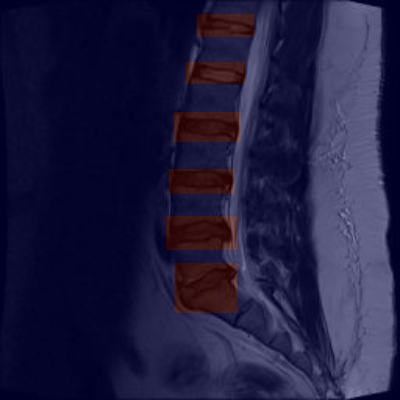

上图展示了我们的模型在腰椎MRI图像上的检测结果。橙色标记区域表示模型识别出的异常椎间盘区域,通过对比这些区域与周围正常组织的差异,可以清晰地看出腰椎间盘突出的程度和位置。这种可视化结果对于临床诊断和治疗方案的制定具有重要参考价值。